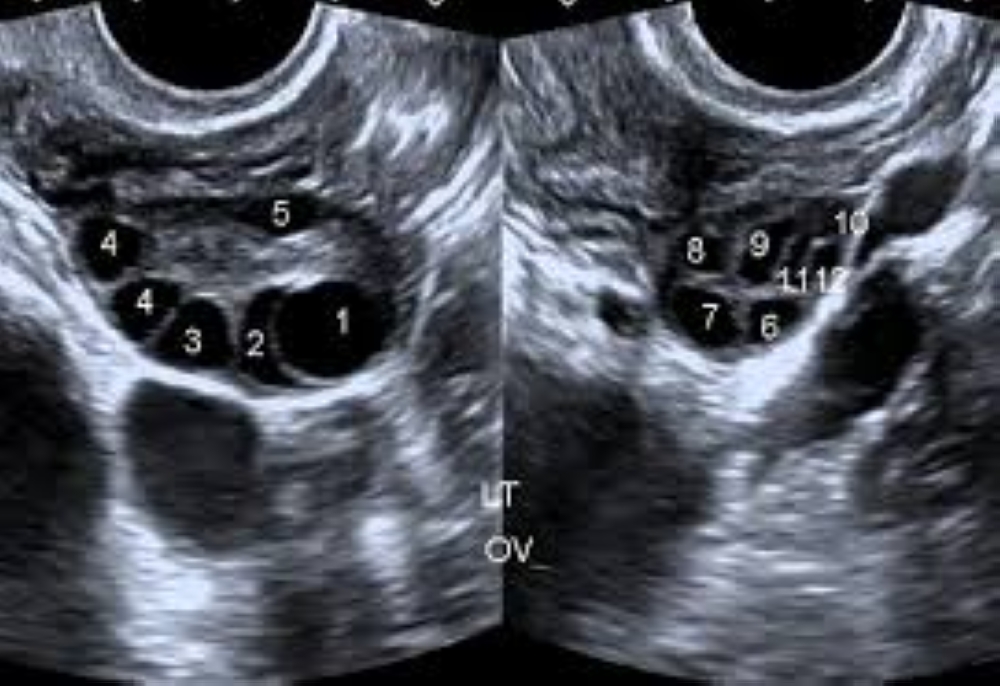

Polycystic Ovary Syndrome (PCOS) is a common condition that affects hormones. In recent years, I have seen many young women seeking treatment for infertility being diagnosed with PCOS. The condition can cause irregular menstrual periods, excessive hair growth, acne, and infertility. Many cases go undetected, and those that are identified are often discovered during investigations for infertility. ALSO READ: How jogging boosts your body and mind PCOS is a hormonal imbalance that occurs when the ovaries, the organs that produce and release eggs, generate excess hormones. Normally, the ovaries produce androgens, some of which are converted into oestrogens, while the rest remain in circulation. In PCOS, however, the ovaries produce higher-than-normal levels of androgens. This disrupts the balance of reproductive hormones, leading to irregular menstrual cycles, missed periods, unpredictable ovulation, or anovulatory cycles, all of which can result in infertility. Affected women may also experience increased facial hair, acne, and, in some cases, male-pattern baldness. ALSO READ: Mitigating health challenges in era of remote work, learning Weight gain is common and further increases the risk of developing diabetes, hypertension, and ischemic heart disease. Symptoms of PCOS are often more severe in obese women. Additionally, PCOS increases the risk of cancer of the inner lining (endometrium) of the uterus. Women can develop PCOS at any time after puberty, though it is most commonly seen in those in their 20s and 30s. The exact cause remains unknown. However, obesity, stress, and elevated androgen levels are considered significant risk factors. Insulin resistance is also believed to contribute to the development of PCOS and diabetes. Studies suggest that individuals with PCOS often have chronic low-grade inflammation, which stimulates the ovaries to produce more androgens. Genetic factors may also play a role, with some women inheriting a predisposition to the condition. A higher prevalence of PCOS has been observed in women involved in intense competitive sports or physically demanding professions such as the police or military, possibly due to higher androgen levels, increased muscle mass, and greater bone density. In PCOS, multiple fluid-filled sacs, or cysts, develop along the outer edge of the ovaries. These cysts contain immature eggs, known as follicles. Unlike in a healthy hormonal cycle, these follicles do not release eggs regularly. As a result, women may have menstrual cycles without ovulation, leading to infertility. In many cases, PCOS is first diagnosed during infertility evaluations. Irregular periods and increased facial hair often raise suspicion of PCOS. Diagnosis is typically confirmed through ultrasound, which reveals multiple fluid-filled cysts. The condition commonly affects both ovaries but may sometimes involve only one, in which case symptoms may be milder. PCOS (Polycystic Ovarian Syndrome) differs from PCOD (Polycystic Ovarian Disease). In PCOD, the ovaries produce many immature eggs, often leading to enlarged ovaries and cyst formation. While the symptoms may be similar, they are generally milder. PCOS is considered a more serious condition, involving significant metabolic and hormonal disturbances, whereas PCOD is largely a lifestyle-related condition. PCOD is usually managed through diet, exercise, and medication, and rarely leads to severe infertility. On ultrasound, PCOD typically shows fewer and smaller cysts compared to PCOS, where cysts are larger and more numerous. Treatment of PCOS includes lifestyle modifications such as a balanced diet, regular physical exercise, and weight management to reduce obesity and insulin resistance. Managing stress through meditation, breathing exercises, and engaging in creative or relaxing activities is equally important. Changes in physical appearance, such as excessive hair growth, can be addressed through cosmetic procedures. Medications may be prescribed to manage metabolic issues, diabetes, hormonal imbalance, and to induce ovulation in women planning to conceive. PCOS is a lifelong hormonal and metabolic disorder that increases the risk of infertility, diabetes, lipid abnormalities, and heart disease. However, with awareness, a healthy lifestyle, timely diagnosis, and appropriate treatment, its long-term complications can be reduced, and many women can successfully conceive. The writer is a specialist in internal medicine.